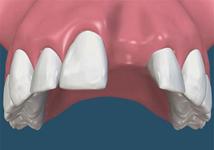

Tyto postupy nám umožní doplnit chybějící množství kosti v čelistech pacienta i zlepšit kvalitu kosti. Většinou se setkáváme s omezenou nabídkou kostní tkáně díky resorpčním (úbytkovým) procesům způsobených věkem či vytržením zubu, přítomností anatomických struktur jako je čelistní dutina, nervový kanál nebo patologických či poúrazových stavů - cysty, zlomeniny.